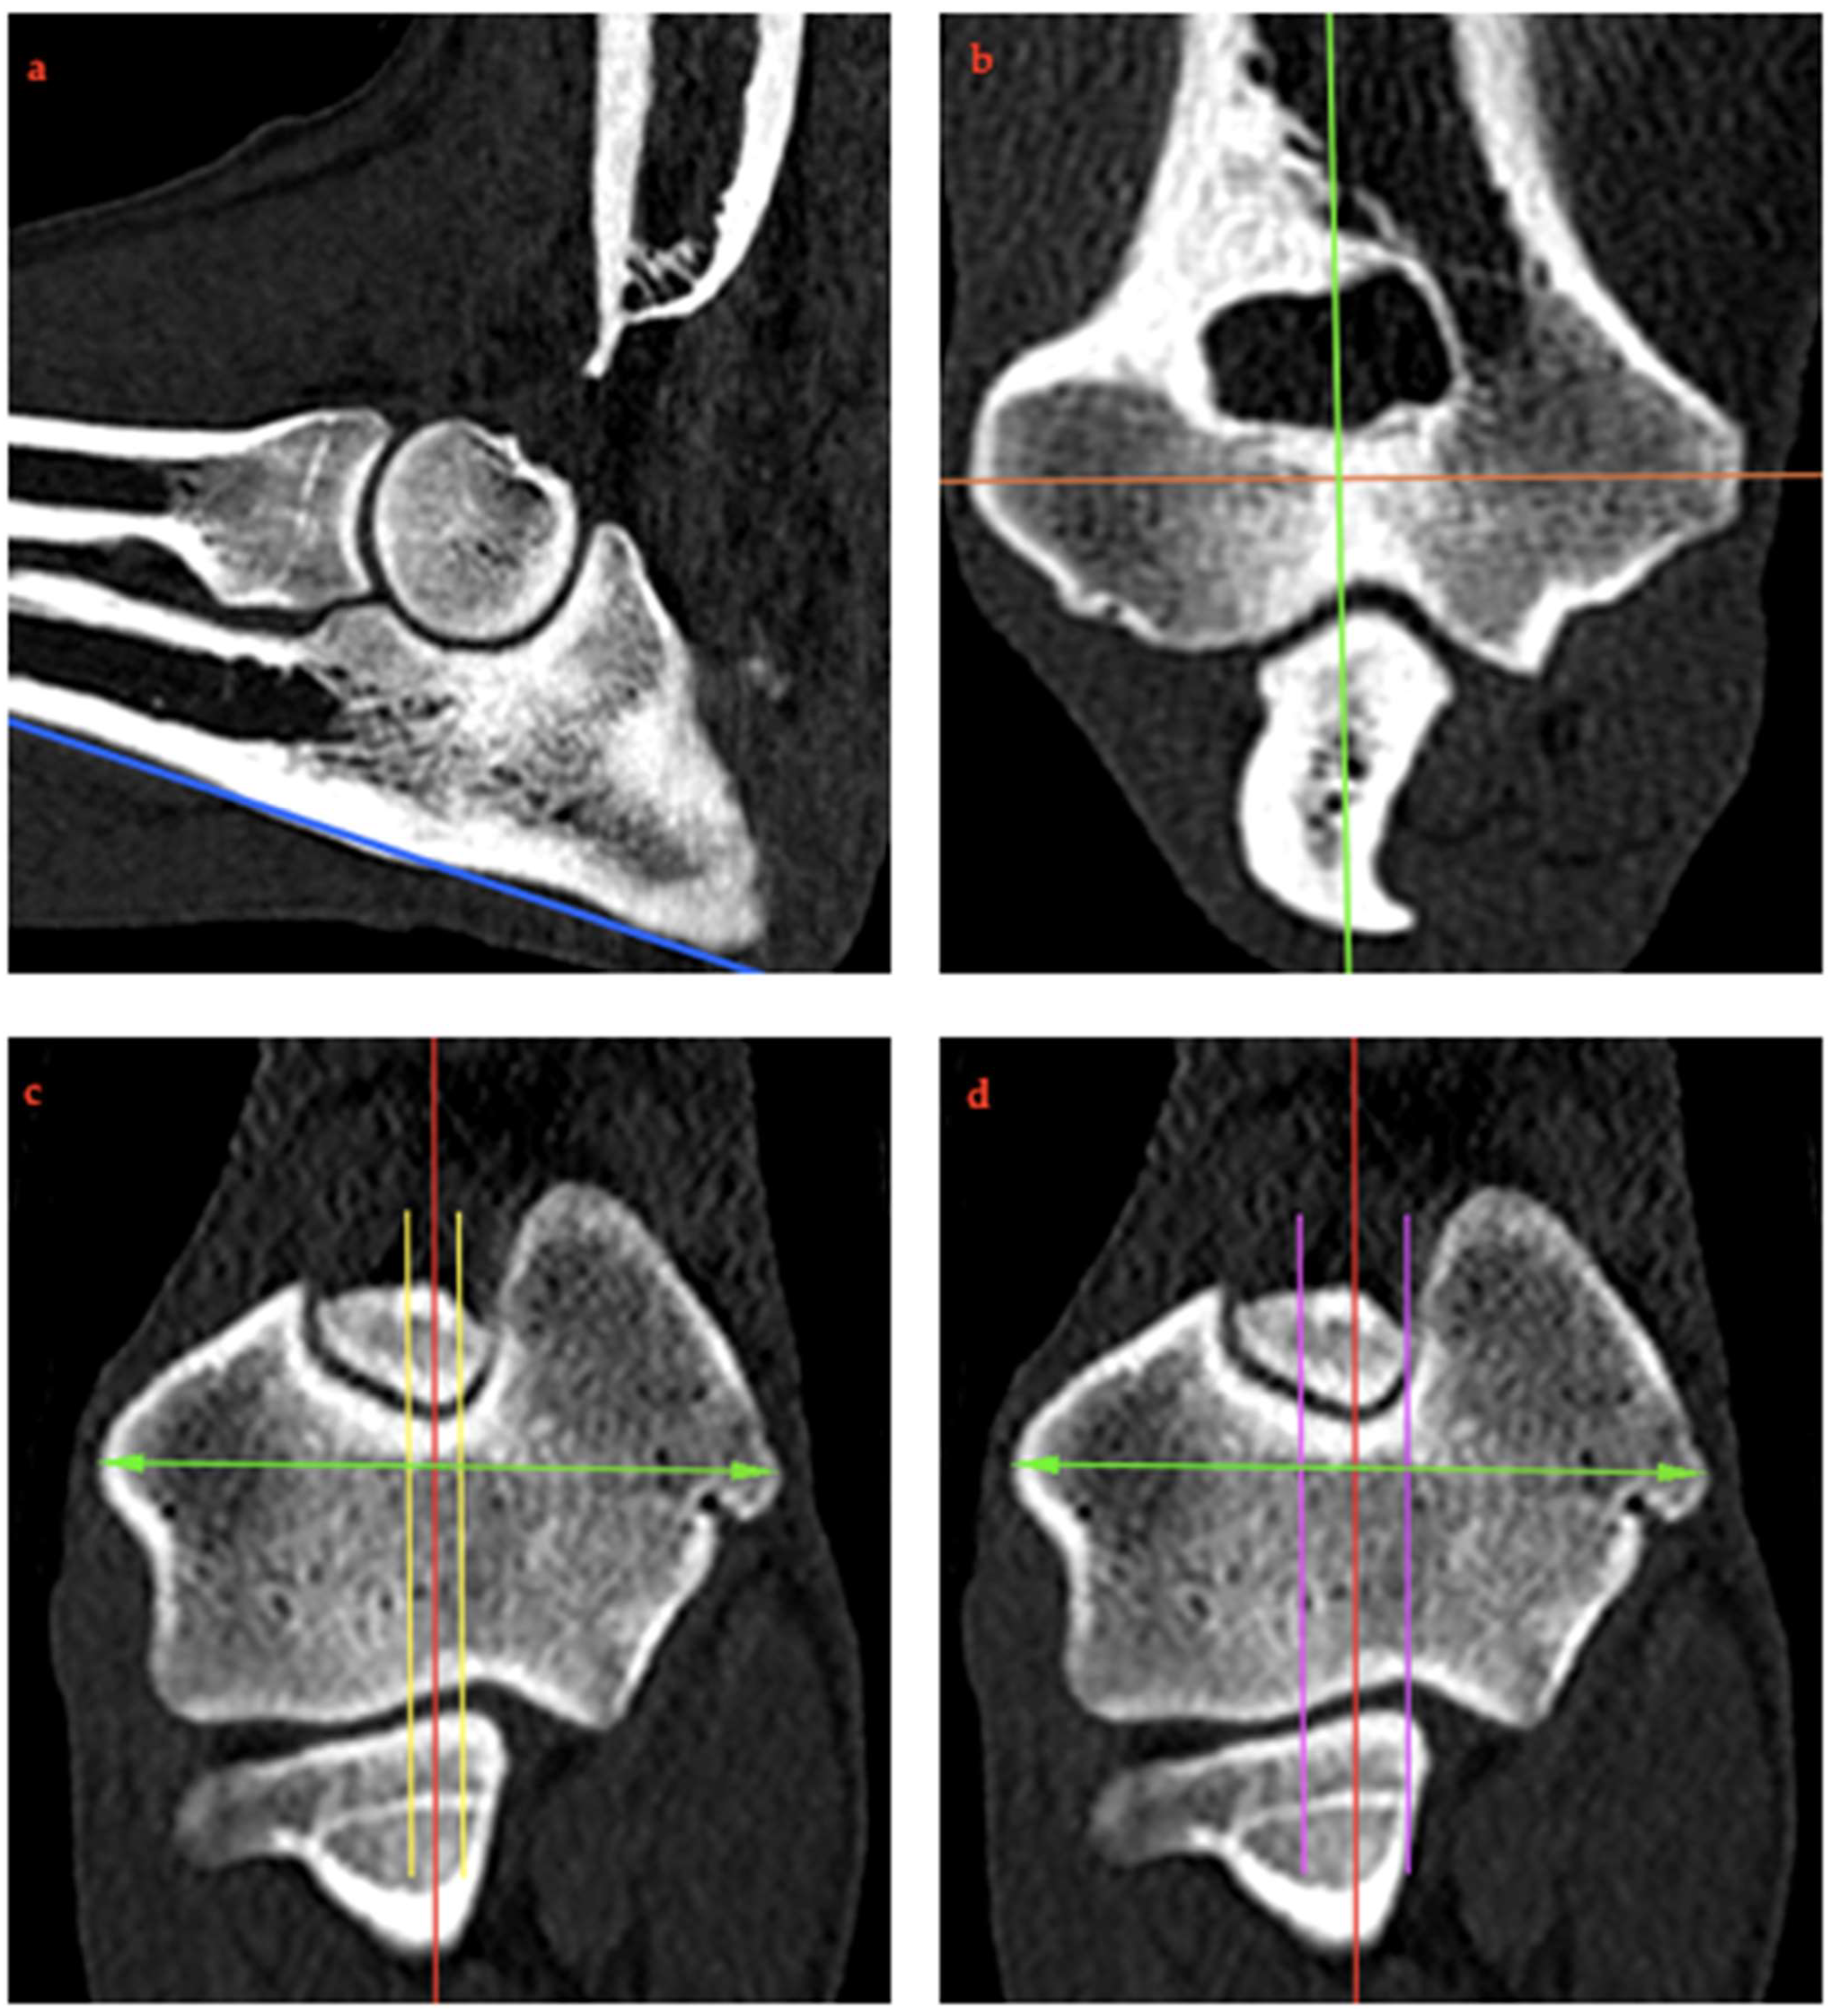

2.4. RUI Measurements